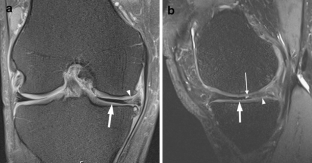

A total of 914 consecutive exams from 875 patients (524 men; mean age, 35 years) were reviewed. Vacuum phenomenon was found in 12 patients (prevalence 1.3%). In six (50%) patients, VP mimicked a meniscal tear, with four cases simulating a torn medial discoid meniscus. The VP signal was not easily differentiated from meniscal signal on most sequences in most cases (9/12). Gradient-recalled echo (GRE) localizer images proved most definitive, with 3D SPACE images the next most effective. Fast spin echo (FSE) images were only occasionally able to differentiate VP from meniscus.

Rarely recognized on MR, VP can mimic meniscal pathology, potentially leading to inappropriate surgery. Because differentiation of VP from the meniscus is challenging on FSE at 3 T, radiologists should become familiar with the appearance of VP and review GRE localizer or 3D images carefully to avoid misinterpretation.